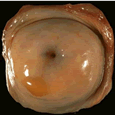

女性生殖系统正面图